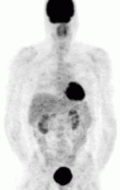

The imaging modalities discussed below are for tumor characterization, confirmation of metastatic disease, and treatment planning — they are not used to discern tumor location or help the surgical team prepare for excision.[92] For most pheochromocytoma patients, functional imaging will follow a CT or MR. If anatomic imaging only demonstrates an adrenal tumor without evidence of disease anywhere else in the body and the metanephrine levels are overtly elevated, functional imaging can be foregone in favor of prompt surgical excision.[87] Over the last decade, there have been five functional techniques used to evaluate the pheochromocytoma patient (1) 18F-fluorodeoxyglucose positron emission tomography (18F-FDG PET), commonly referred to as the PET scan, (2) iodine-123 meta-iodobenzylguanadine (123I-MIBG), (3) 18F-flurodihydroxyphenylalanine (18F-FDOPA),(4) 68Ga-DOTA coupled somatostatin analogs (68Ga-DOTA),(5).[93] 11C-Hydroxy ephedrine(HED-PET).

MIBG Scintigraphy — the pheochromocytoma is appreciated in the left panel on the right side of the screen (right panel; left side of the screen) as the darkened circle towards the abdomen. The darkened structure at the head of the patient is the thyroid gland, while the darkened structure in the pelvis of the patient is the bladder. This is normal physiologic uptake.

The first functional imaging technique utilized in pheochromocytoma patients was 123I-MIBGscintigraphy. Given the compound's similar structure to the catecholamine norepinephrine (secreted by pheochromocytomas), MIBG was well-suited for uptake by most neuroendocrine tumors.[94] Furthermore, if a patient was found to be positive on an MIBG scan, they were eligible for MIBG treatment, offering additional avenues for those with widespread metastatic disease.[95] However, further investigation revealed that while MIBG excelled with adrenal lesions, it was far less superior in patients with extra-adrenal paragangliomas, particularly with specific genetic variants like those in the succinate dehydrogenase subunit–encoding genes (SDHx).[83] As the positron emission tomography scans were developed, MIBG has slowly lost its favor for the pheochromocytoma patient.[83]

FDG PET — the tumor is appreciated as the dark structure in the patient's left chest. The darkened structure at the head of the patient is the brain, posterior to the abdomen are the kidneys, and in the pelvis is the bladder. These are normal.

Of the four above mentioned modalities, 18F-FDGPET is the most common and readily available functional imaging technique at most hospital systems, but the least-specific to neuroendocrine tumors (Image Left). In 2012, over 200 patients participated in a trial that compared the current gold standard of the time (MIBG/CT/MRI) to the novel FDG PET. Compared to its functional counterpart, FDG outperformed MIBG in detecting soft-tissue and bone metastases with higher specificity in patients with biochemically active tumors.[83]